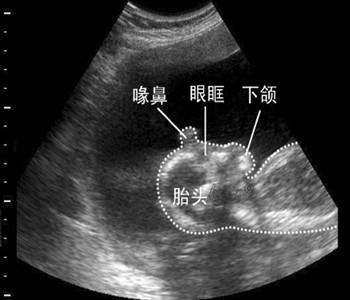

1、月份小的胎儿

对于月份很小的胎儿,一般在流产时都采取药物的方式,用药物将胎儿“扼杀”在女性的腹中,然后再排出女性的身体。这种被排出的胎儿,最终归宿就是流进了马桶里,随着旋转的抽水被带进了下水管、地下水道,再也看不见。